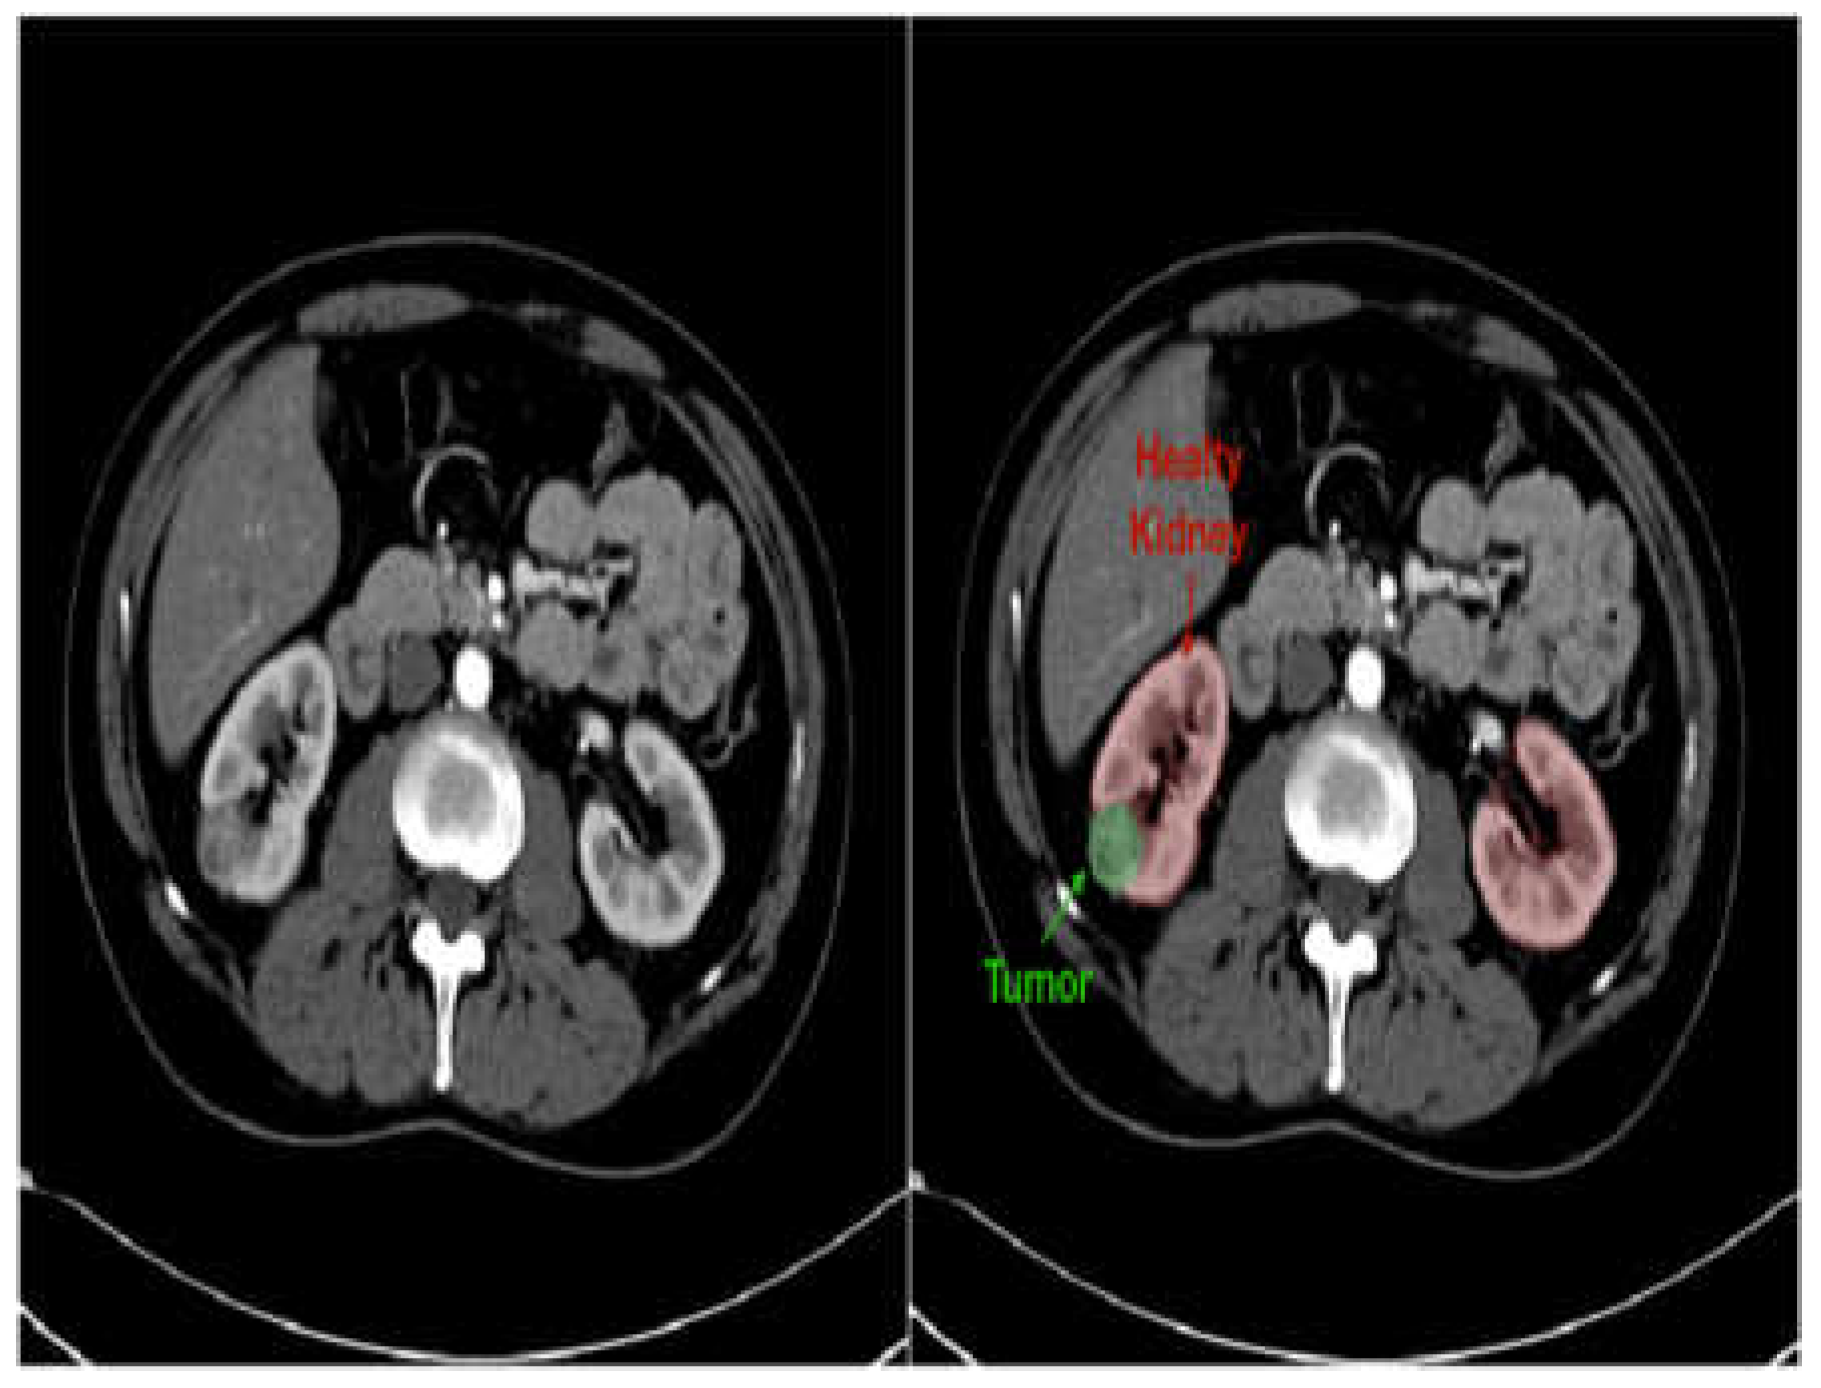

Figure 7. Kidney CT image in grayscale (left) and with overlaid mask (right) to highlight suspected stones or tumors [41].

• Improved Diagnostics: AI-driven image analysis tools can enhance the identification and description of pediatric kidney cancers and tumors. Radiologists can spot minor abnormalities, characterize renal masses, and estimate tumor burden more accurately by using ML algorithms that have been trained on large datasets of pediatric renal images (Figure 7). AI algorithms provide early identification of kidney cancers and tumors by methods including pattern recognition, masking, segmentation, and quantitative analysis, allowing for confident diagnosis and timely treatment [19].